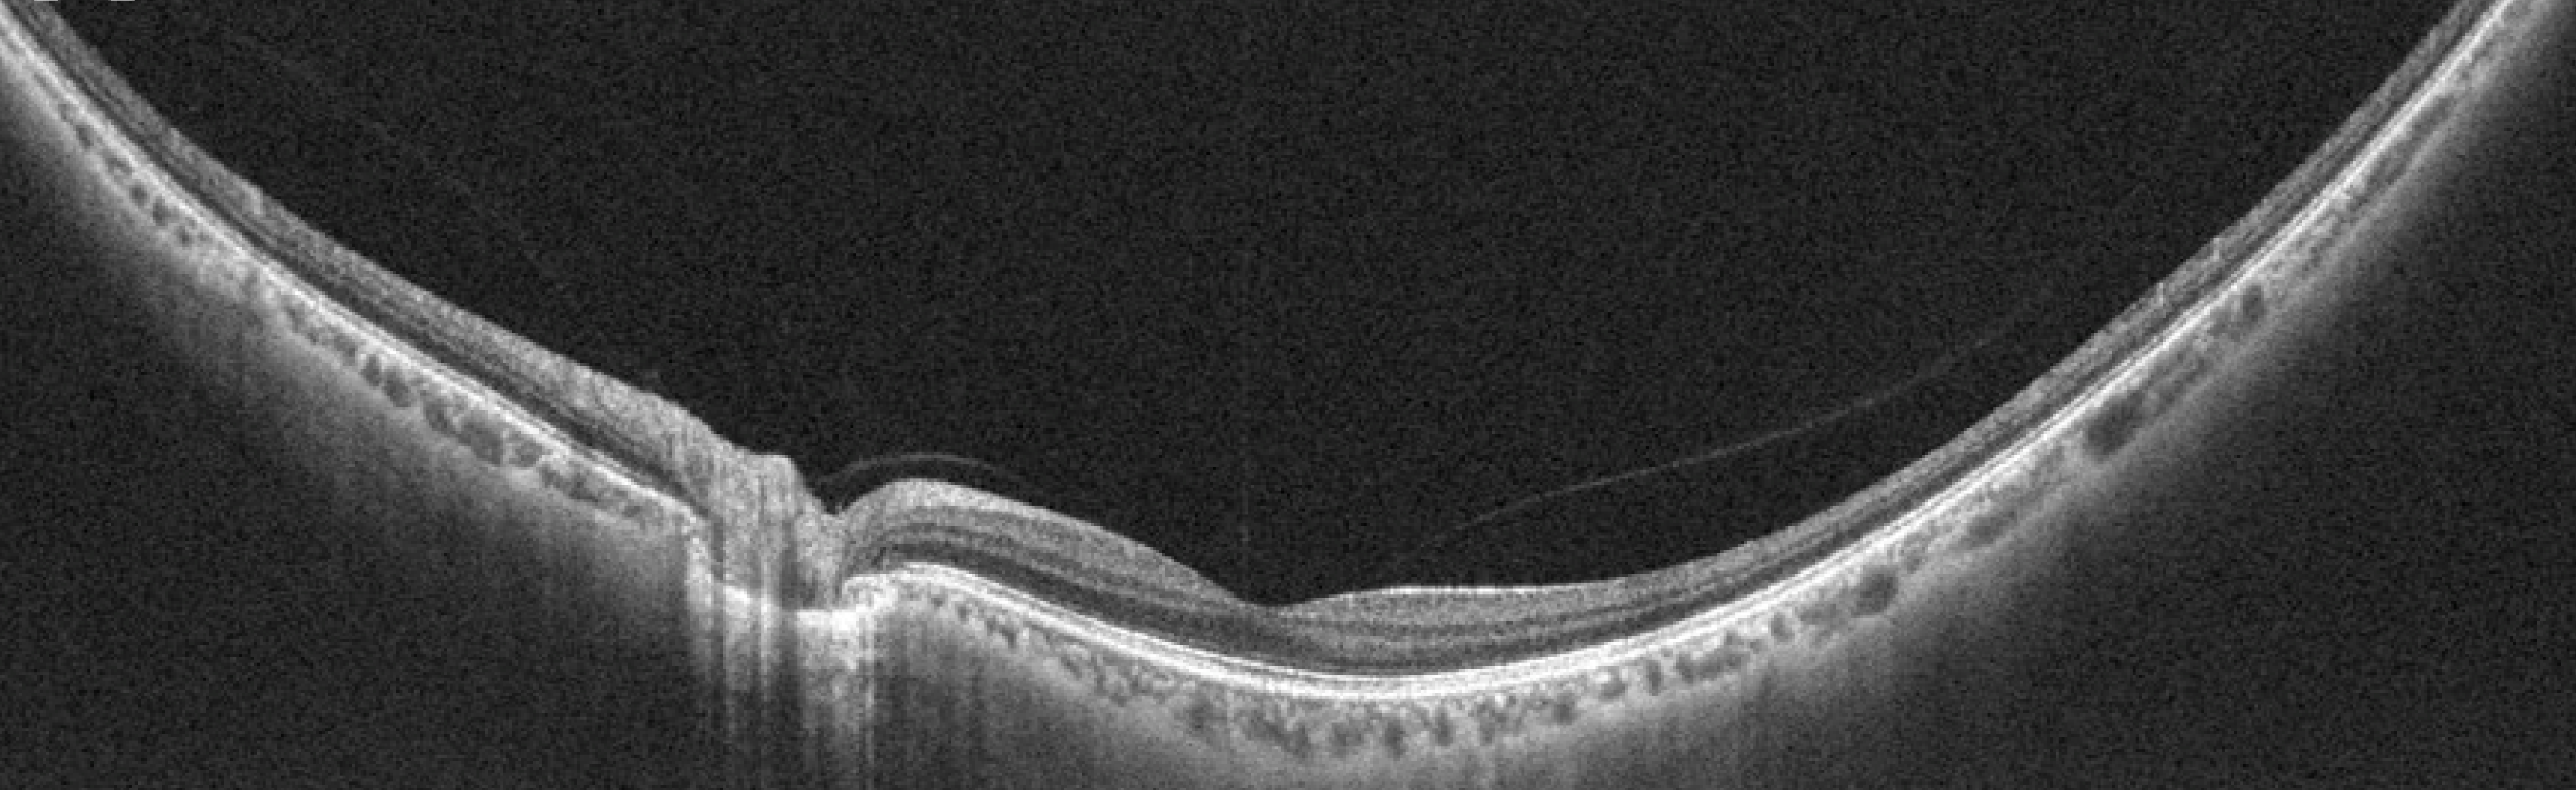

OCT Atlas is free resource developed for eye care students and professionals to refresh their skills in interpreting optical coherence tomography (OCT) scans.